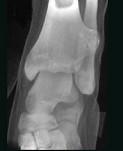

问题 女,35岁,左侧外踝可扪及一硬结,有轻压痛,请结合影像学检查,选出最可能的诊断()

选项 A.骨瘤 B.骨软骨瘤 C.骨巨细胞瘤 D.骨肉瘤 E.骨样骨瘤

答案 B